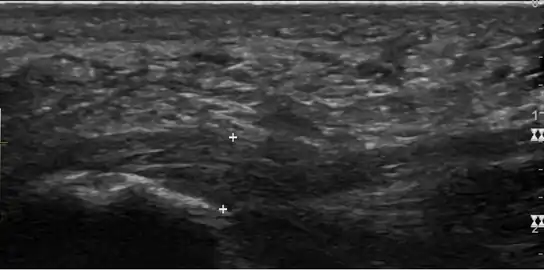

a)Ultrasonographic finding of plantar fasciitis b)normal sonographic finding -

Thickened plantar fascia in ultrasound

The plantar fascia has three fascicles-the central fascicle being the thickest at 4 mm, the lateral fascicle at 2 mm, and the medial less than a millimeter thick.[18] In theory, plantar fasciitis becomes more likely as the plantar fascia's thickness at the calcaneal insertion increases. A thickness of more than 4.5 mm ultrasound and 4 mm on MRI are useful for diagnosis.[19] Other imaging findings, such as thickening of the plantar aponeurosis, are nonspecific and have limited usefulness in diagnosing plantar fasciitis.[13]